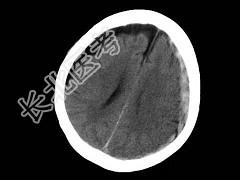

- 单项选择题男,38岁, 外伤后半个月,行CT复查如图, 最可能的诊断为 ( )

A、脑出血

B、硬膜外血肿

C、脑萎缩

D、脑挫裂伤

E、亚急性硬膜下血肿